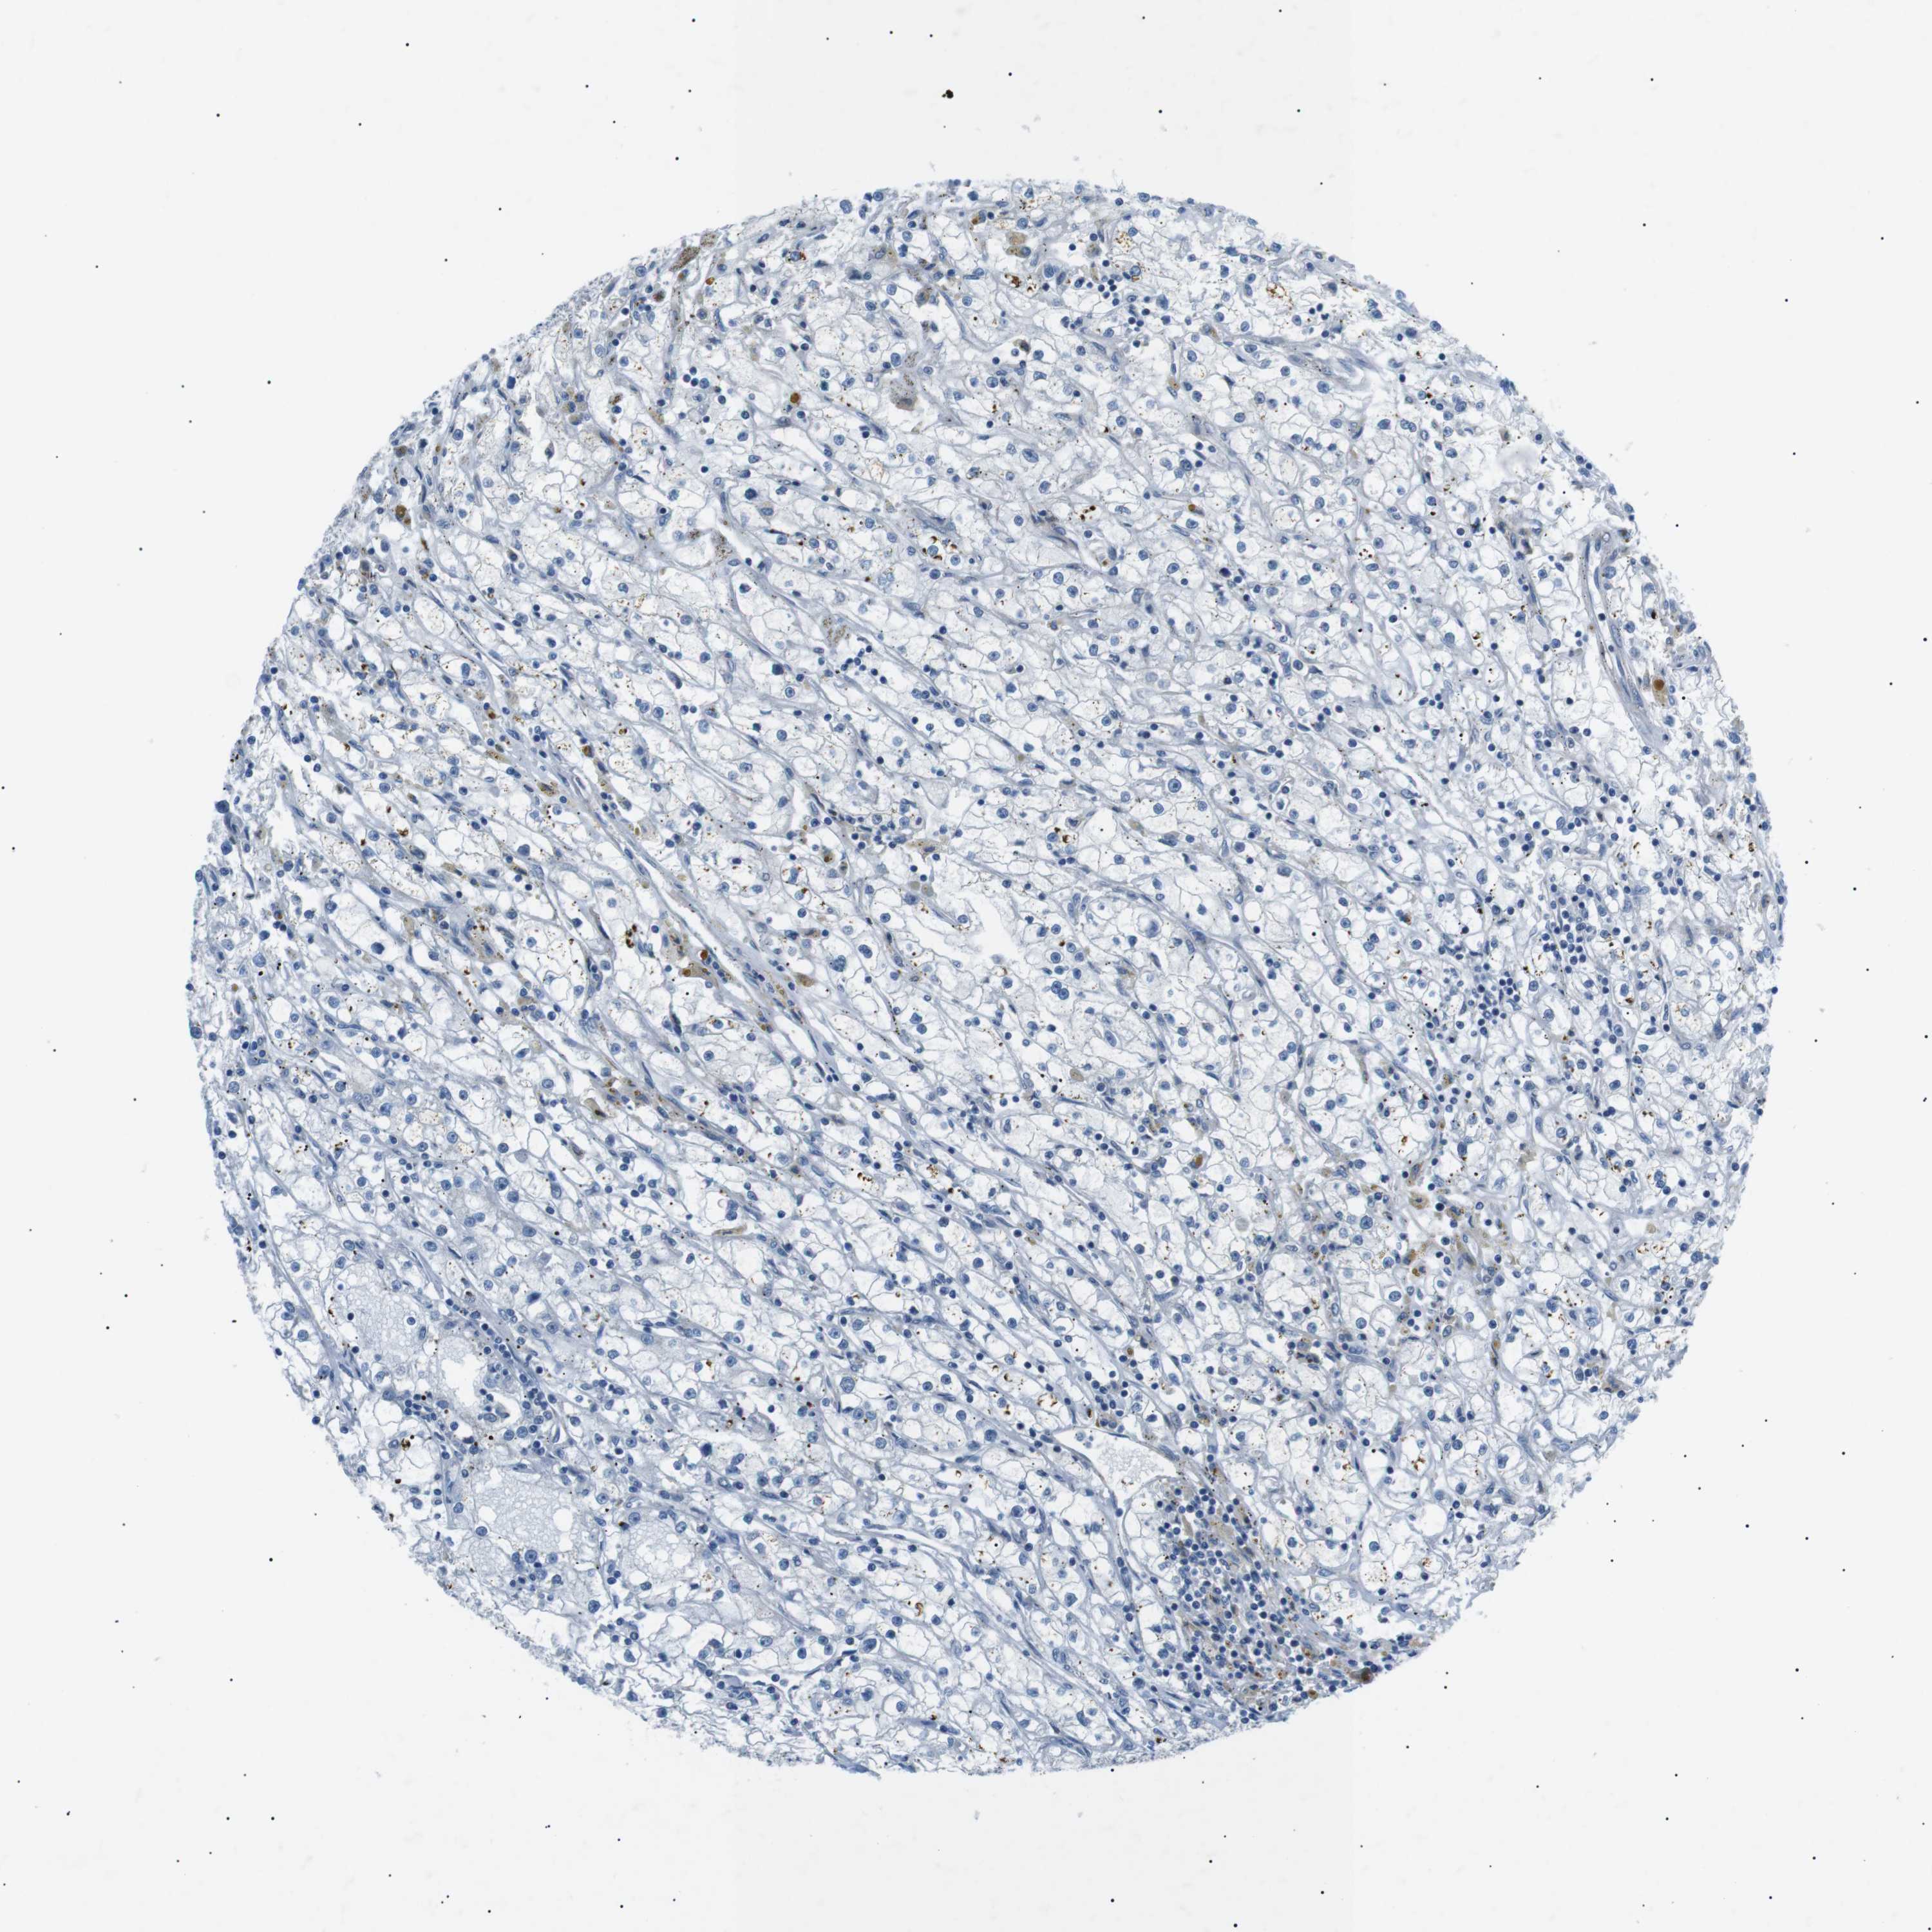

CANCER RENAL CANCER Show tissue menu

KICH TCGA KIRC TCGA KIRC VALIDATION KIRP TCGA PROTEIN RCC CPTAC PROTEIN EXPRESSION

KIDNEY CHROMOPHOBE (TCGA) - Interactive survival scatter ploti

The Survival Scatter plot shows the clinical status (i.e. dead or alive) for all individuals in the patient cohort, based on the same data that underlies the corresponding Kaplan-Meier plots. Patients that are alive at last time for follow-up are shown in blue and patients who have died during the study are shown in red.

The x-axis shows the expression levels (FPKM) of the investigated gene in the tumor tissue at the time of diagnosis. The y-axis shows the follow-up time after diagnosis (years). Both axes are complimented with kernel density curves demonstrating the data density over the axes. The top density plot shows the expression levels (FPKM) distribution among dead (red) and alive patients (blue). The right density plot shows the data density of the survived years of dead patients with high and low expression levels respectively, stratified using the cutoff indicated by the vertical dashed line through the Survival Scatter plot. This cutoff is automatically defined based on the FPKM cutoff that minimizes the p-score. The cutoff can be changed by dragging the vertical line or by entering a cutoff value in the square labeled "Current cut-off".

Under the Survival Scatter plot the p-score landscape (black curve; left axis) is shown together with dead median separation (red curve; right axis). Dead median separation is the difference in median mRNA expression between patients who have died with high and low expression, respectively. It is calculated as follows: median FPKM expression of dead patients with high expression - median FPKM expression of dead patients with low expression. This is intended to aid the user in visually exploring custom cutoffs and the associated p-scores and dead median separation.

Individual patient data is displayed and can be filtered by clicking on one or more of the category buttons on the top of the page. Categories describing expression level and patient information include: high, low, alive, dead, female, male and tumor stages. The scale of the x-axis can be toggled between linear and log-scale by clicking on the "x log" button. Mouse-over function shows TCGA ID, patient information and mRNA expression (FPKM) for each patient.

& Survival analysisi

Kaplan-Meier plots summarize results from analysis of correlation between mRNA expression level and patient survival. Patients were divided based on level of expression into one of the two groups "low" (under cut off) or "high" (over cut off). X-axis shows time for survival (years) and y-axis shows the probability of survival, where 1.0 corresponds to 100 percent.

ARID5B is not prognostic in Kidney Chromophobe (TCGA)